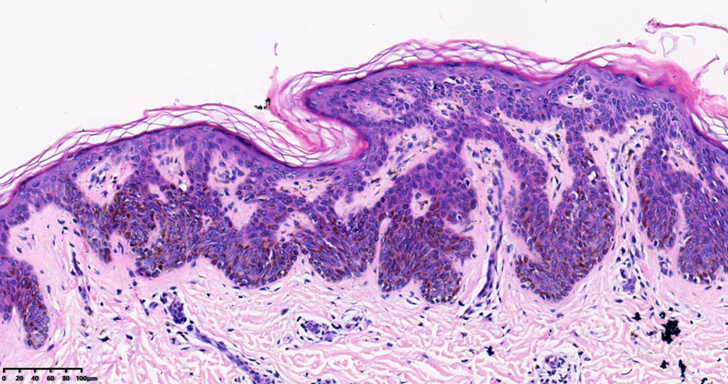

病理显微镜下表现为分化好的基底细胞呈疣状、乳头状或结节状增生,并位于表皮水平面以上,棘层肥厚、角化过度,常有角质囊肿形成,增生的表皮中可有较多色素。